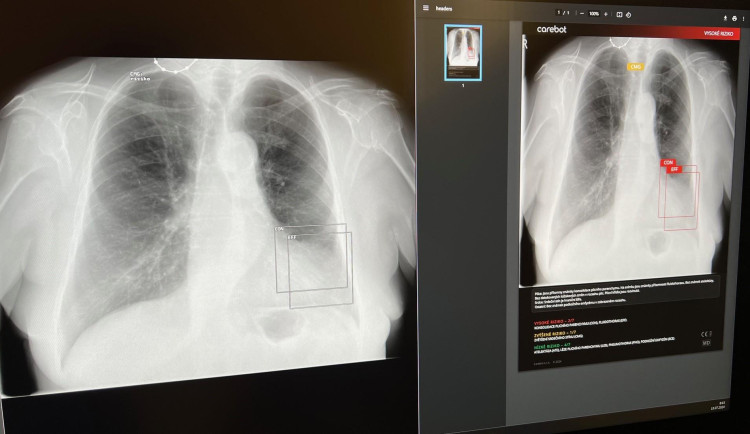

V táborské nemocnici pomáhá lékařům s diagnostikou plic umělá inteligence

Umělá inteligence mění způsob, jakým se poskytuje zdravotní péče. Jednou z posledních novinek v oblasti medicíny je systém Carebot, který byl nasazen na radiologickém oddělení Nemocnice Tábor.